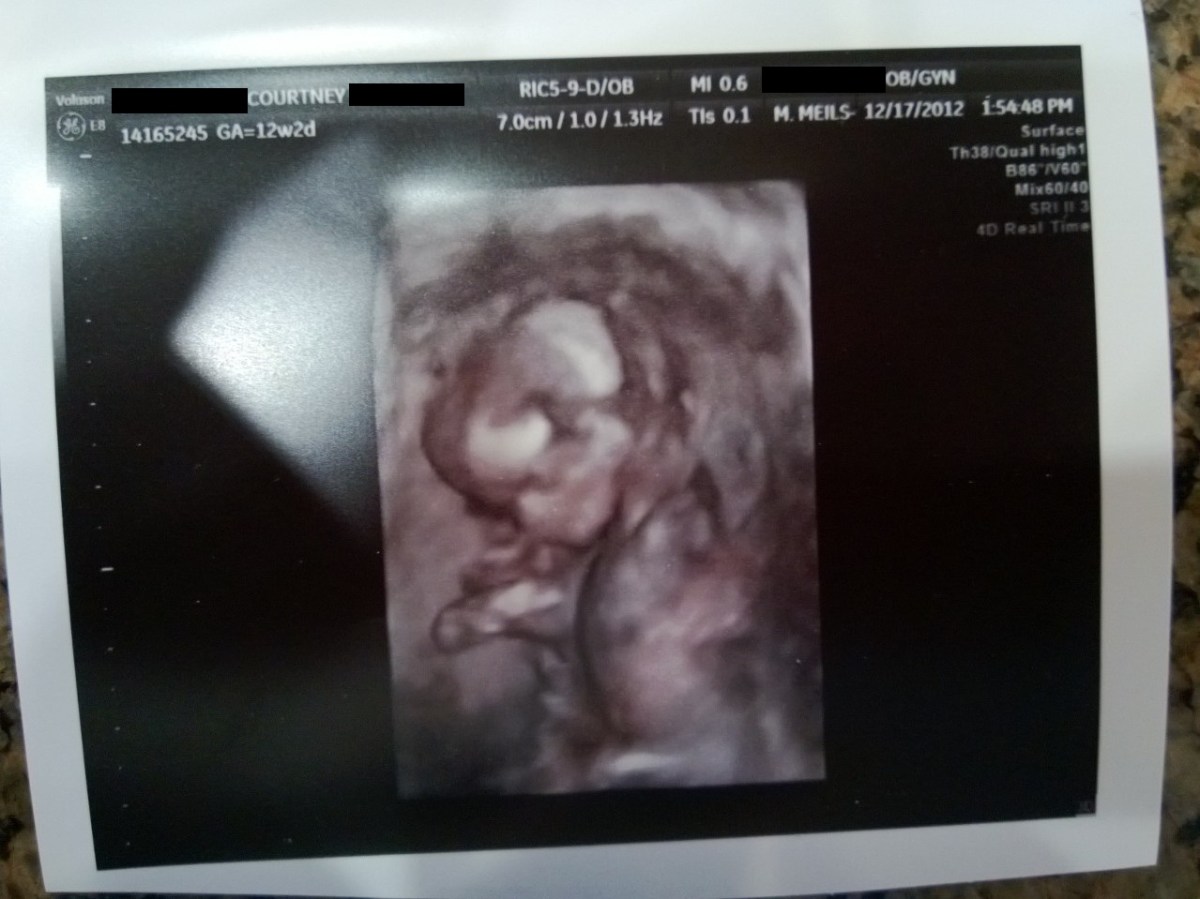

WP_20121217_019 December 17, 2012 by Courtney Leave a comment ← Previous Image Next Image → 12w2d – Looking cute! Like Loading...